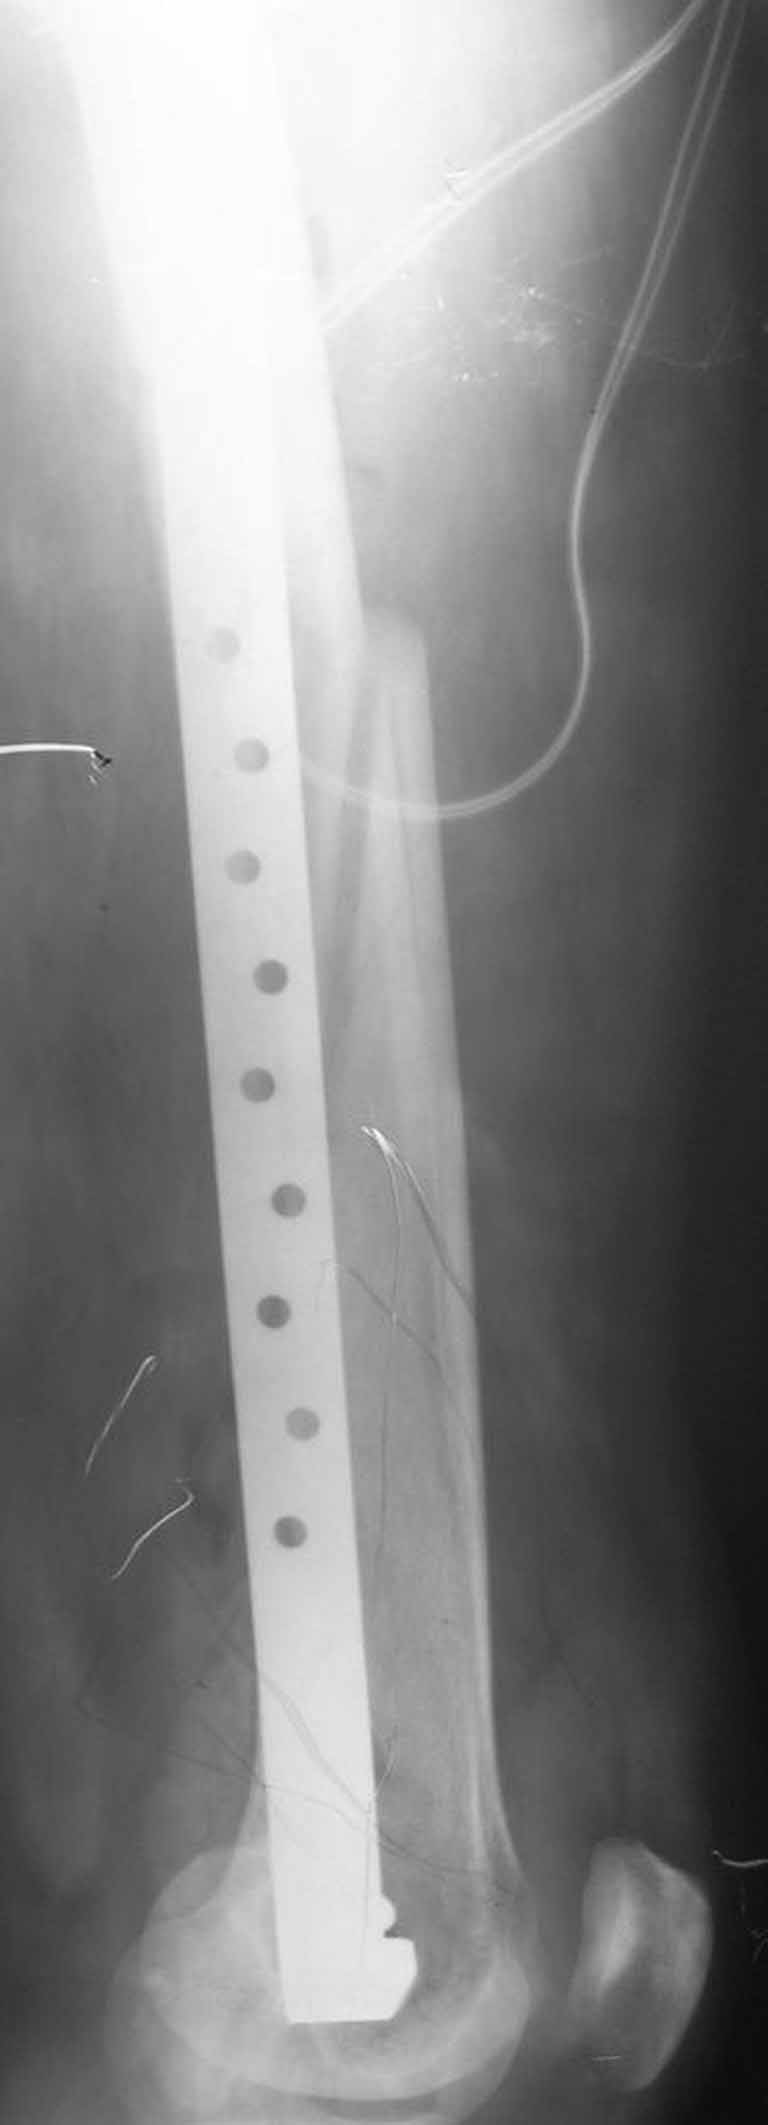

Представляю вам один из наших недавних случаев выполнения малоинвазивного остеосинтеза бедренной кости обычной пластиной 95 градусов. Длина восстановлена с помощью дистрактора (по сути это основная и б(о)льшая часть репозиции). Произведено два небольших доступа, проведена спица направитель. Рентген-контроль для подтверждения достаточной длины/оси (ЭОП использовался в другой операционной). Создание туннеля обратной стороной фиксатора. Поворот фиксатора, введение клинка по спице. Фиксация проксимального и дистального концов пластины.

[ Ответить ]

Получилось очень симпатично, поздравляю и восхищаюсь мастерством.

Хотя закрытый остеосинтез блокированным гвоздем выглядит технически проще, особенно при диафизарных переломах. Не говоря о биомеханических преимуществах внутрикостного имплантата, еще меньшей инвазивности, возможности динамизации при проблемах со сращением... Стоимость гвоздей и пластин сопоставимая, на рынке есть масса отечественных предложений.